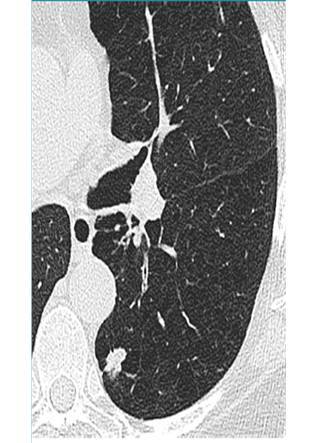

Define nodule, and mass

•Rounded opacities measuring up to 3 cm and greater than 3 cm, respectively.

What abnormality do you see here?